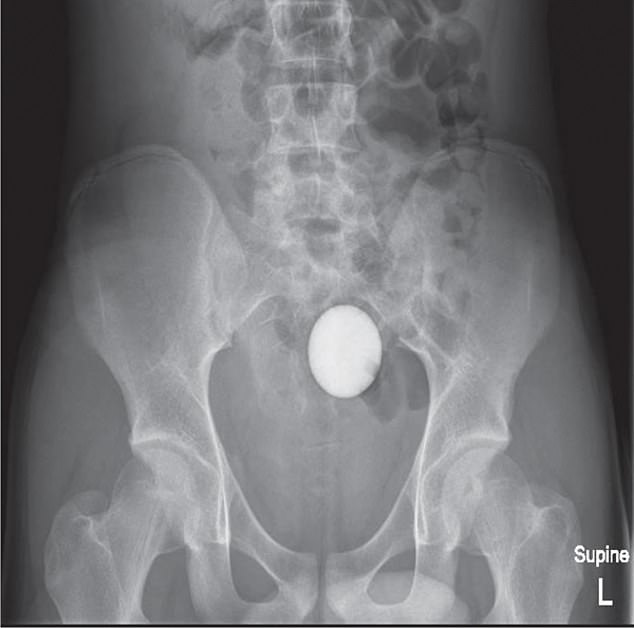

X-ray scans showed it had made its way to his sigmoid colon, the last part of the large intestine, which connects to the rectum.

However, an X-ray performed 24 hours later showed it was still there.